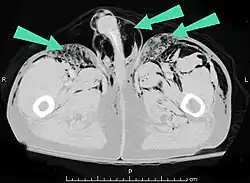

Additionally, it may result from self-injection of air during illicit drug use, particularly in individuals who inject substances intravenously or into unusual sites. There have been documented cases of subcutaneous emphysema occurring in various body regions, including the scrotum, secondary to such self-induced air injection during substance abuse.[23]

Air can be trapped under the skin in necrotizing infections such as gangrene, occurring as a late sign in gas gangrene,[2] of which it is the hallmark sign. Subcutaneous emphysema is also considered a hallmark of Fournier gangrene.[27] Symptoms of subcutaneous emphysema can result when infectious organisms produce gas by fermentation. When emphysema occurs due to infection, signs that the infection is systemic (i.e. that it has spread beyond the initial location) are also present.[9][21]

Subcutaneous emphysema is usually benign.[1] Most of the time, SCE itself does not need treatment (though the conditions from which it results may); however, if the amount of air is large, it can interfere with breathing and be uncomfortable.[29] It occasionally progresses to a state "Massive Subcutaneous Emphysema" which is quite uncomfortable and requires surgical drainage. When the amount of air pushed out of the airways or lung becomes massive, usually due to positive pressure ventilation, the eyelids may swell so much that the patient cannot see. The pressure of the air may impede the blood flow to the areolae of the breast and skin of the scrotum or labia which can lead to necrosis. The latter are urgent situations requiring rapid, adequate decompression.[30][31][32] Severe cases can compress the trachea and do require treatment.[33]